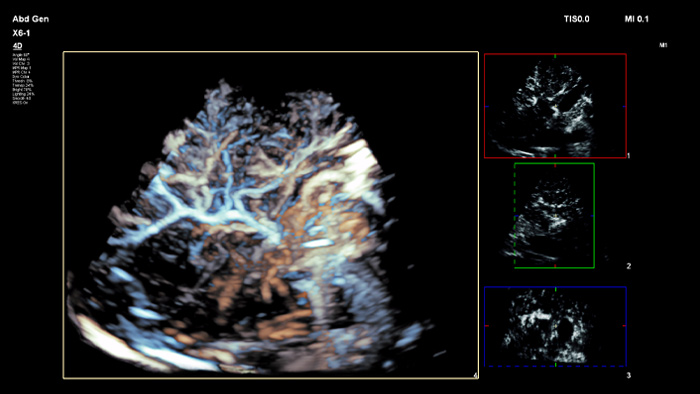

Mit der Tumorkontur können Anwender Läsionen mit einem halbautomatischen Tool planen und hervorheben. Es erleichtert das Zeichnen einer 3D-Kontur um die relevante Struktur und bietet so Unterstützung in schwierigen Fällen, bei denen die Läsion nicht einfach zu erkennen ist.

Jeder Mensch ist anders. Die PureWave Kristalltechnologie bietet ein verbessertes Eindringvermögen bei schwer schallbaren Patienten ohne Abstriche bei der Detailauflösung, der Doppler-Empfindlichkeit und dem kontrastmittelverstärkten Ultraschall (CEUS).

Die PureWave Kristalltechnologie ist der größte Durchbruch bei piezoelektrischem Schallkopfmaterial seit 40 Jahren und ist 85 % effizienter als herkömmliche piezoelektrisches Schallkopfmaterial, was zu herausragenden Ergebnissen bei unterschiedlichsten Patienten führt.